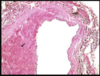

Aneurysm wall histology

66

Pathophysiology: a systemic vascular disease of smooth muscle; caused by **autosomal dominant mutations of the Notch 3gene on chromosome 19**, the protein of which acts as a cell-cell adhesion molecule with nuclear transcription regulatory properties I. Transcription regulatory properties require cleavage of the Notch 3 protein by γ-secretase and transport to the nucleus ii. Notch 3 protein in the cell membrane binds the delta ligand on neigh-boring cells iii. Notch 3 gene is located very close to the CACNL1A4gene that is mutated in familial hemiplegic migraine (1) Sporadic mutation in 15% of patients with characteristic MRI ab- normalities and no family history b. Histology: **fibrosis of the tunica adventitia and granular deposits in the tunica media that develop in arteries of 100–400 mm in diameter (penetrating arteries)** i. Deposits are of an unknown composition that is not amyloid ii. Deposits surround the smooth muscle cells, and also occur in muscle and skin arteries in some patients c. Symptoms: onset between 30–50 years of age i. Recurrent lacunar stroke and TIA, often occurring in the thalamus and sparing the cortex ii. Dementia (30%): usually develops > 10 years after the first stroke from a combination of multiple strokes (i.e., a vascular dementia) and progressive leukoencephalopathy iii. Migraine with aura (25%): does not develop in childhood like other migraines, and typically involves fever and/or stupor {confusional migraine (see pg. 154)} iv. Mood disorders: develop early in the disease course